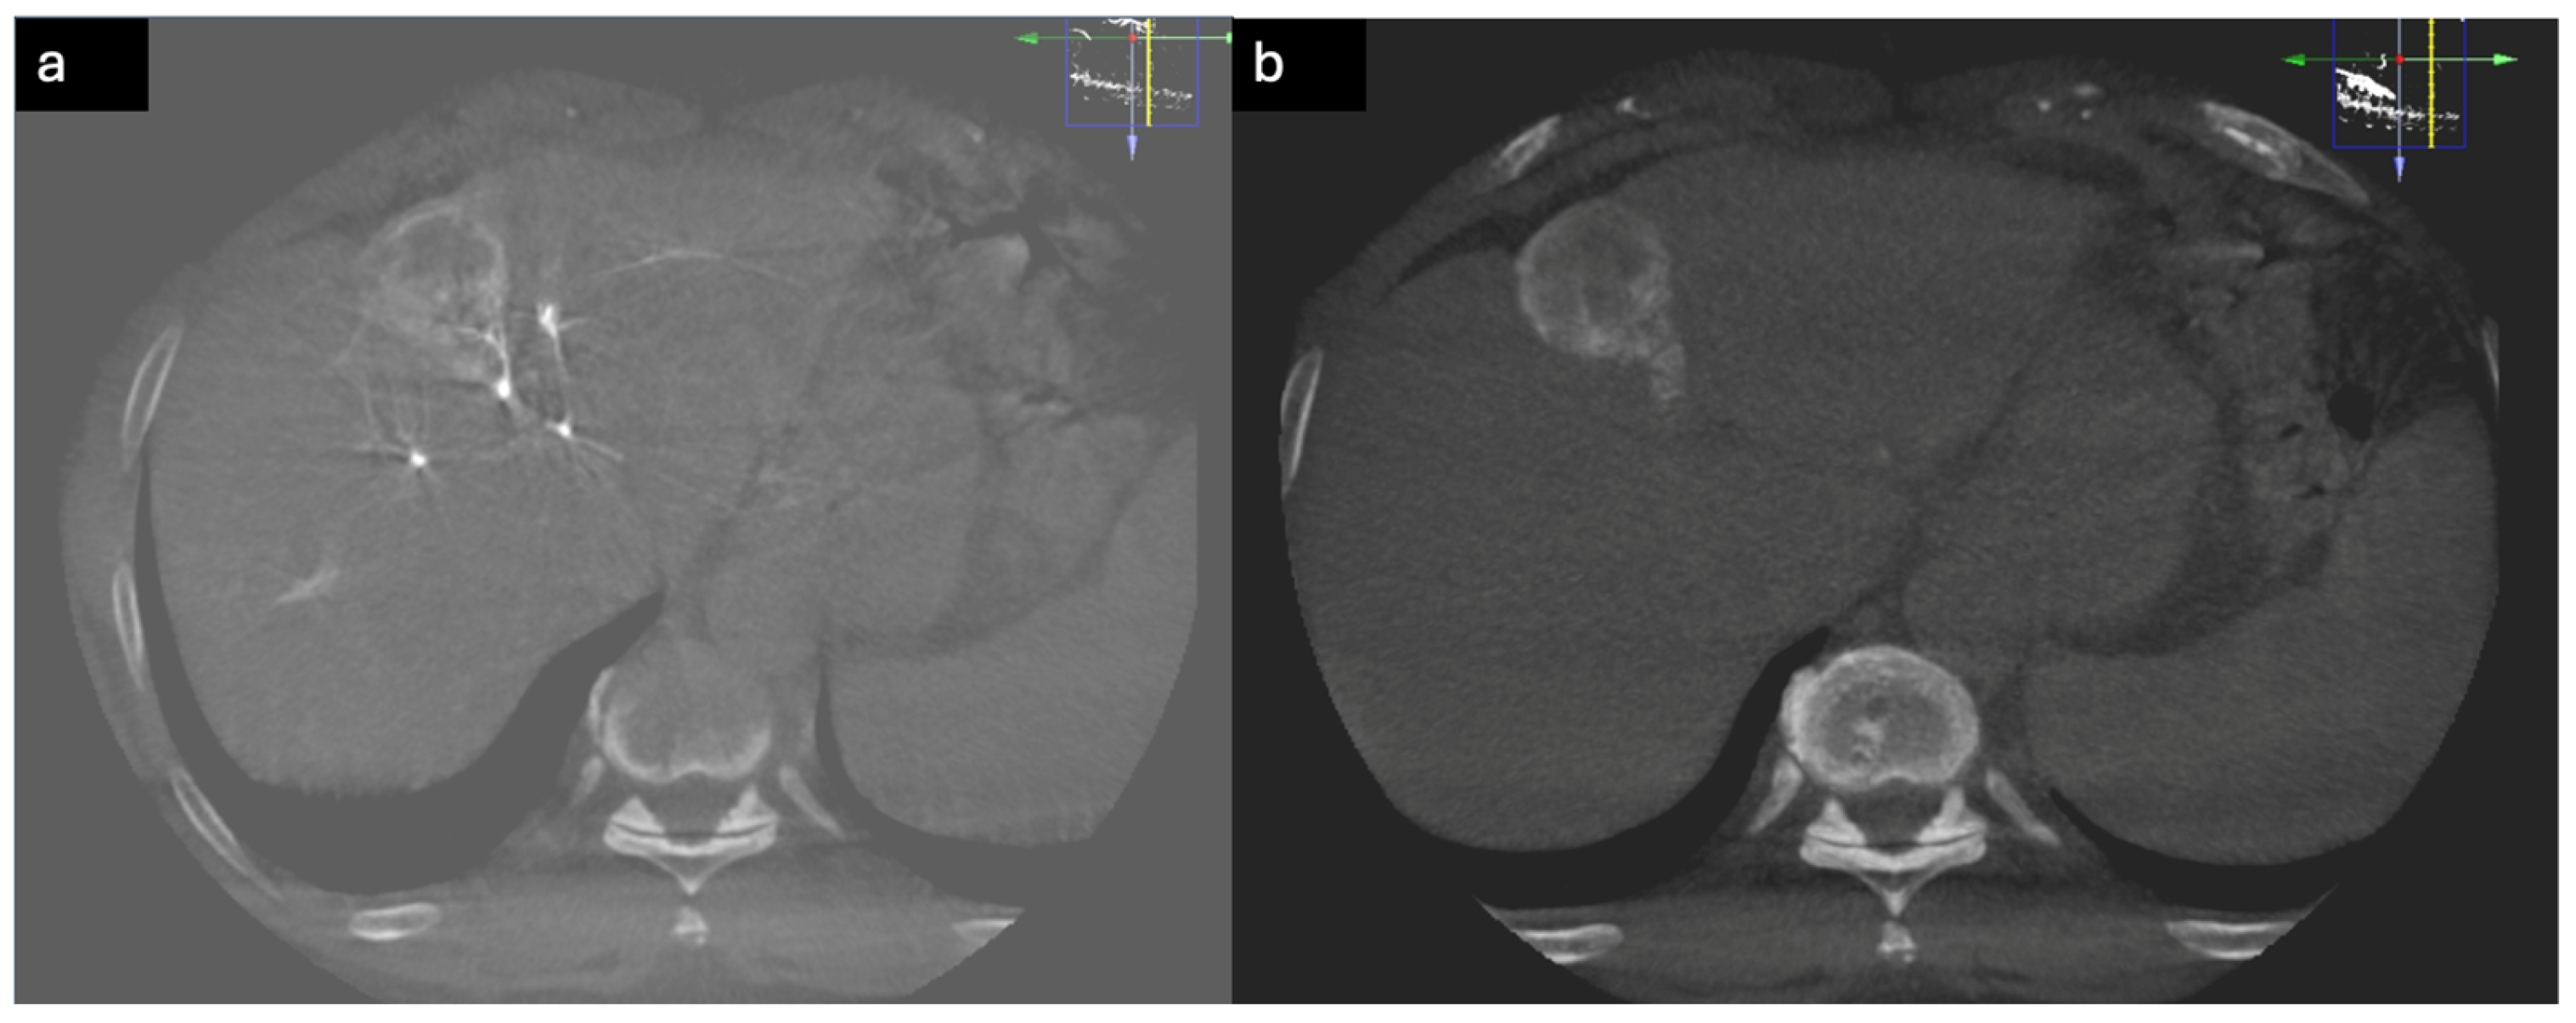

6. Additive Role of Cone-Beam CT